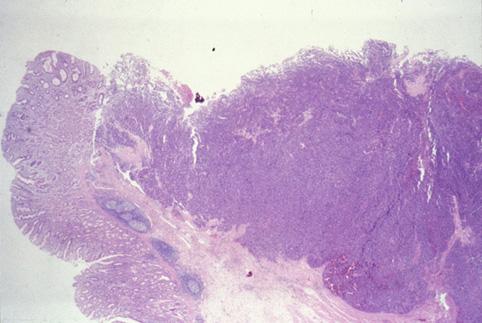

질환(병리주체)의 분류 악성 상피성종양/기타

부위(장기별) 위(부위)/분문

검사방법 마이크로

종양의 육안분류 1형(종괴형)/

종양의 최대경(밀리미터) 40이상

종양의 심달도 s(a)